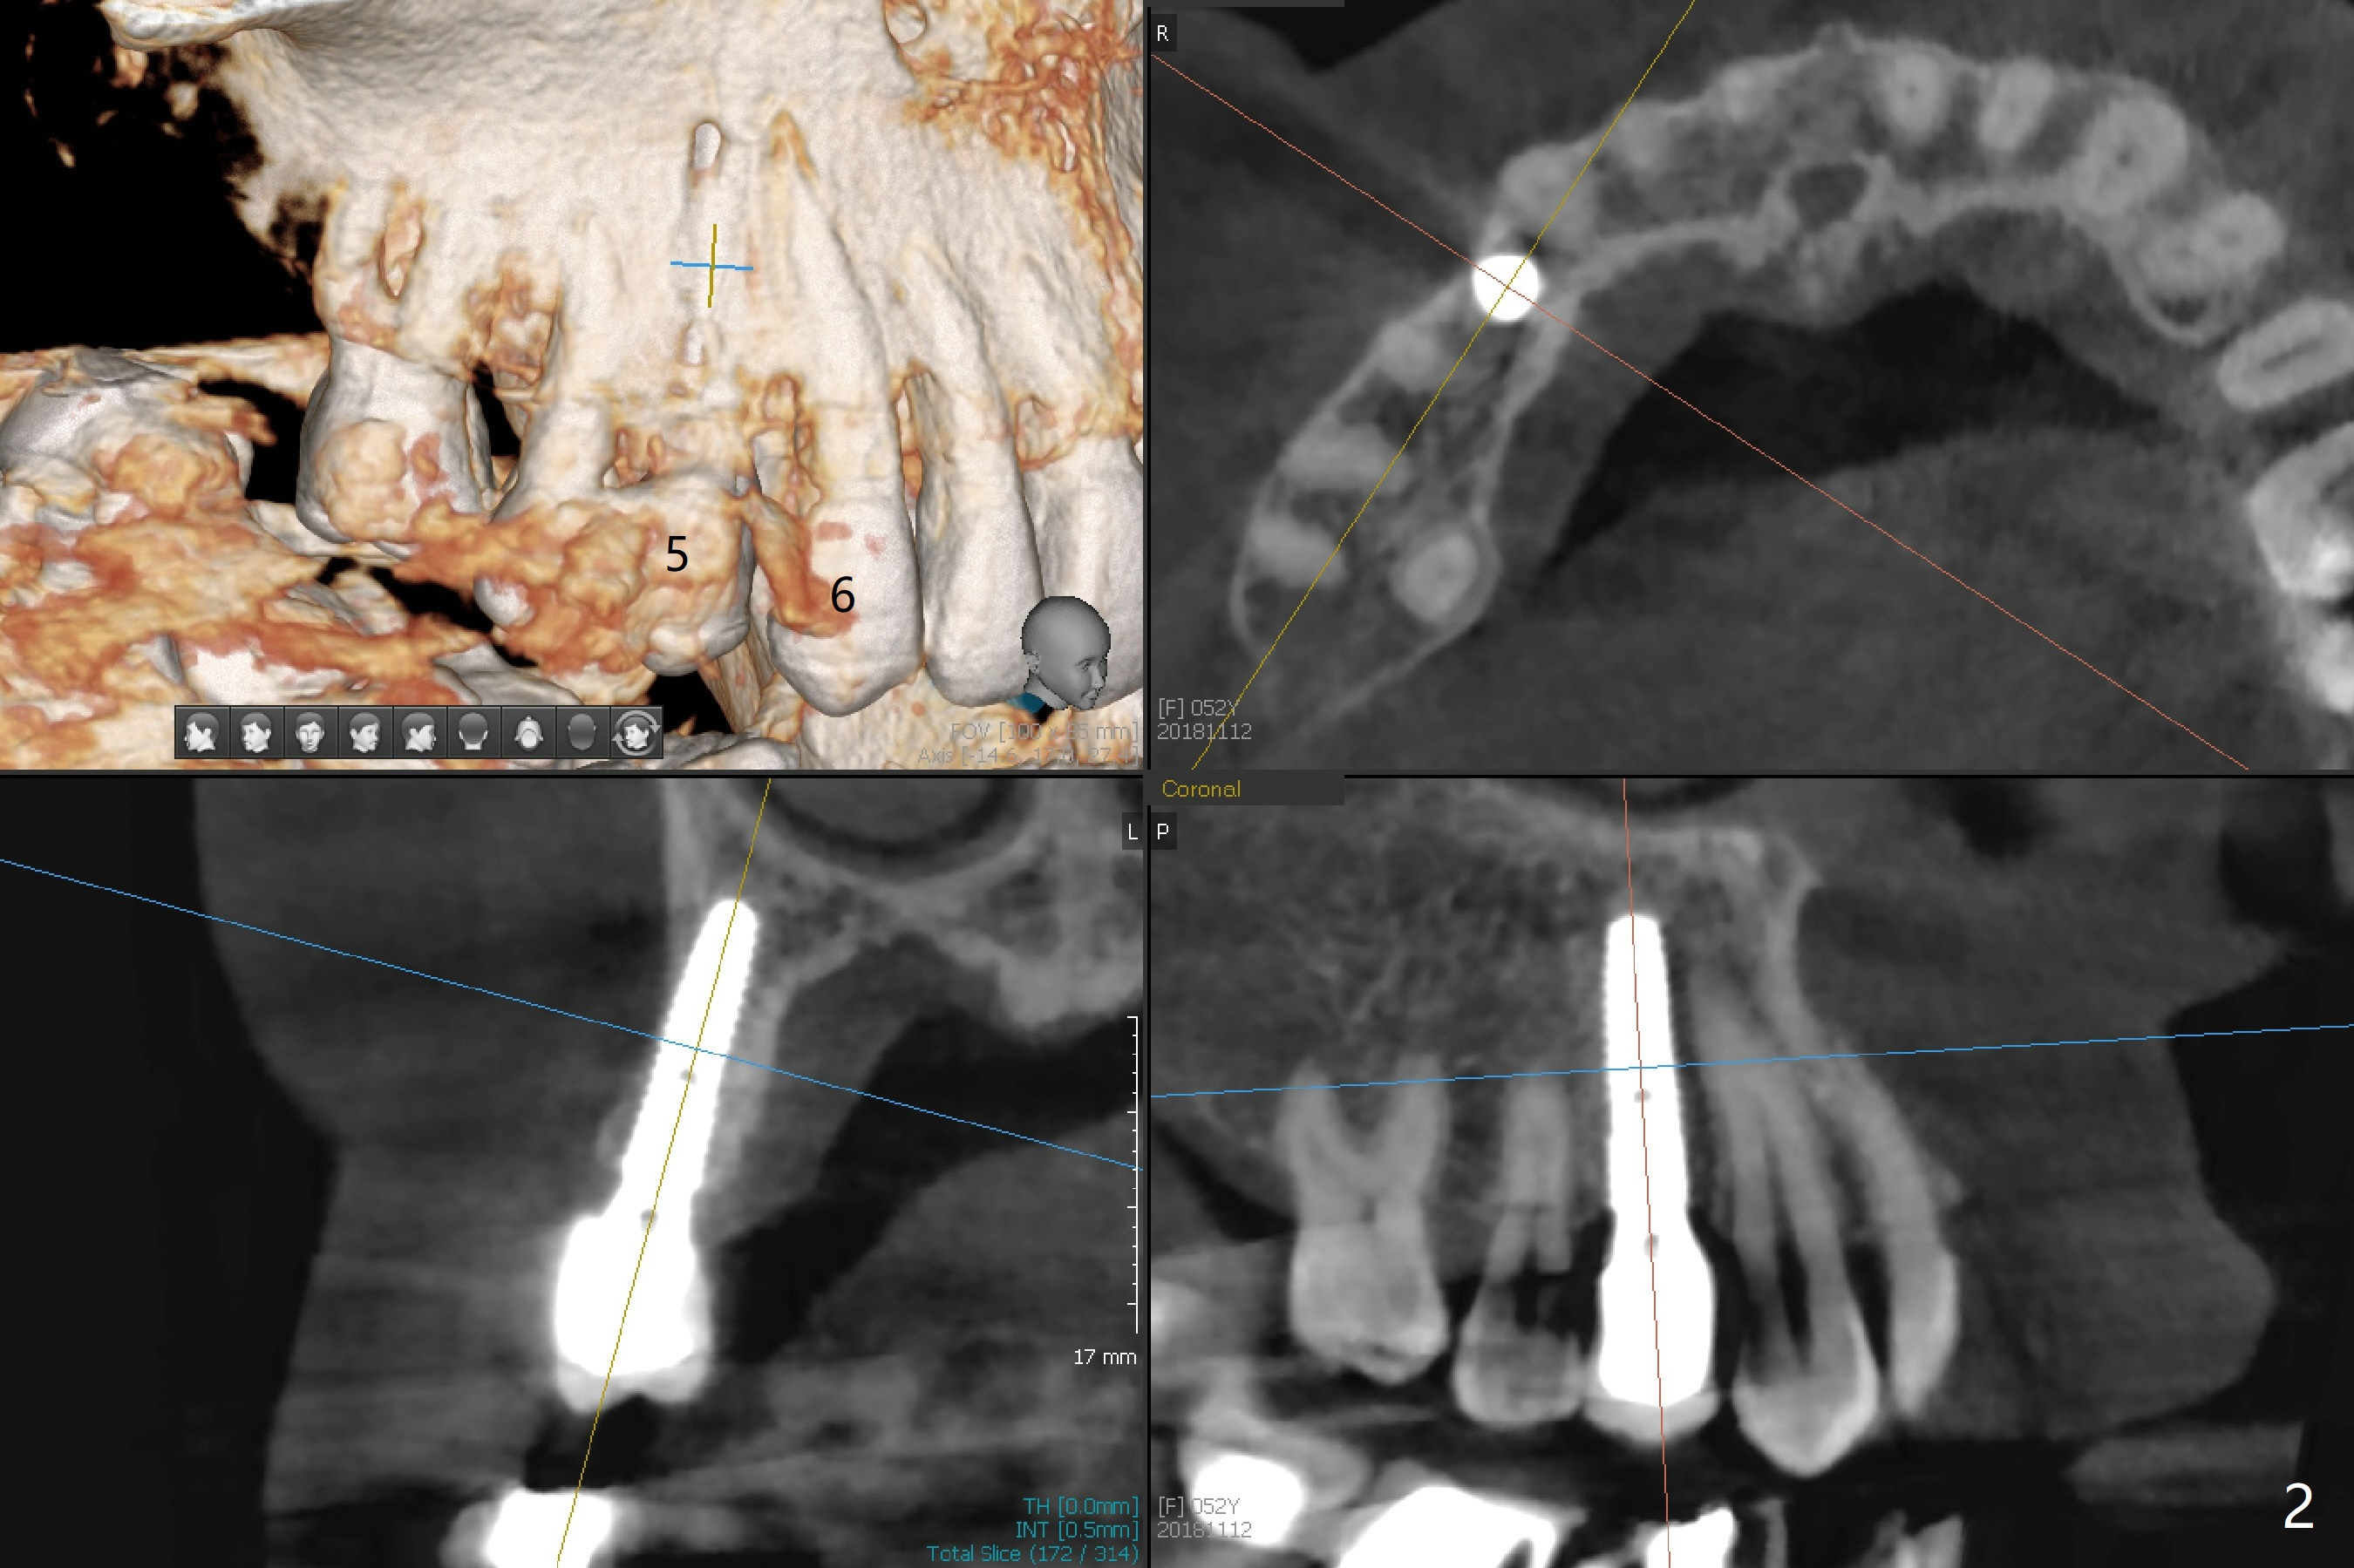

A 52-year-old woman requests an implant at #19 (Fig.1). Her other 2 concerns are the diastema between #5 implant crown and the tooth #6 (Fig.1 (^),2) and whether the tooth #20 is stable enough for crown after sectioning #18-20 FPD and RCT (Fig.1,3 (disto(*)-buccal (B) bone loss)). The ridge at #19 seems to be narrow; a 4x10 mm IS implant appears to be appropriate for the site (Fig.4). Since Magicore has a narrow core and aggressive fins, a 4.0 or 4.5x9(3) mm implant is apparently a good fit. After osteotomy, remove guide, use perio probe to determine crest level and place Magicore